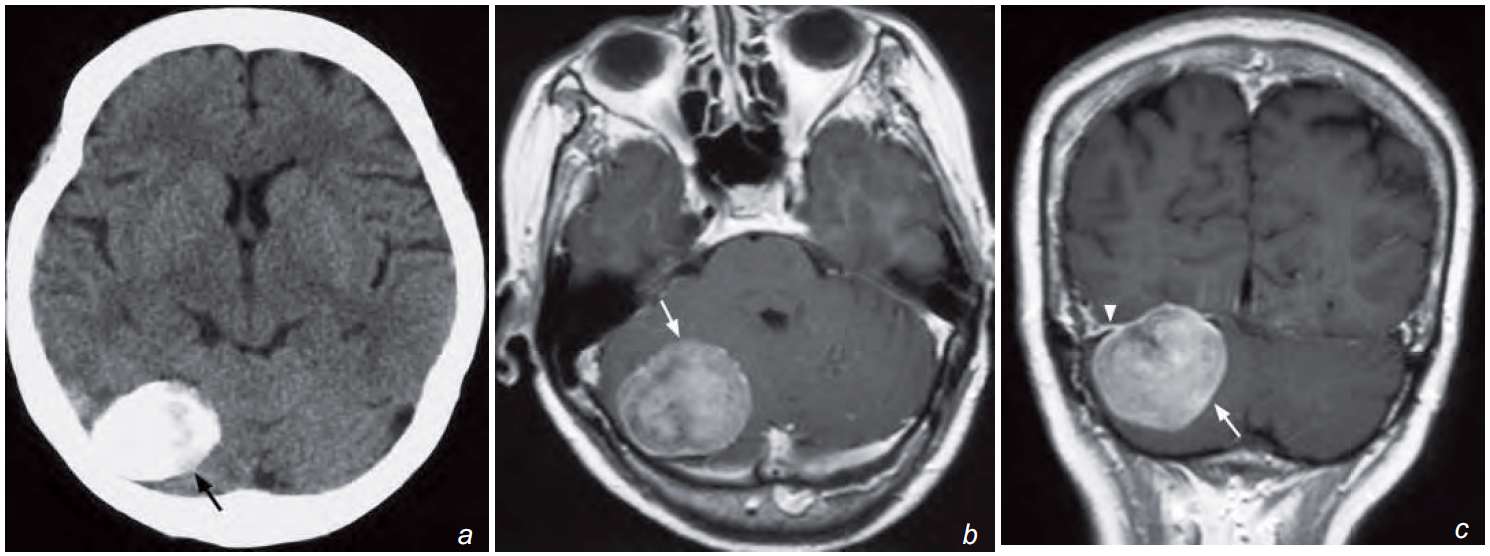

A 68-year-old woman complained of increasing headache and unsteady gait in the past 9 months. Physical examination revealed subtle cerebellar signs but no other neurological deficit. A non-contrast CT and subsequent MRI of the brain were performed for further investigation.

What is seen on the non-contrast CT and contrast enhanced T1W MR image, and what is the diagnosis ?